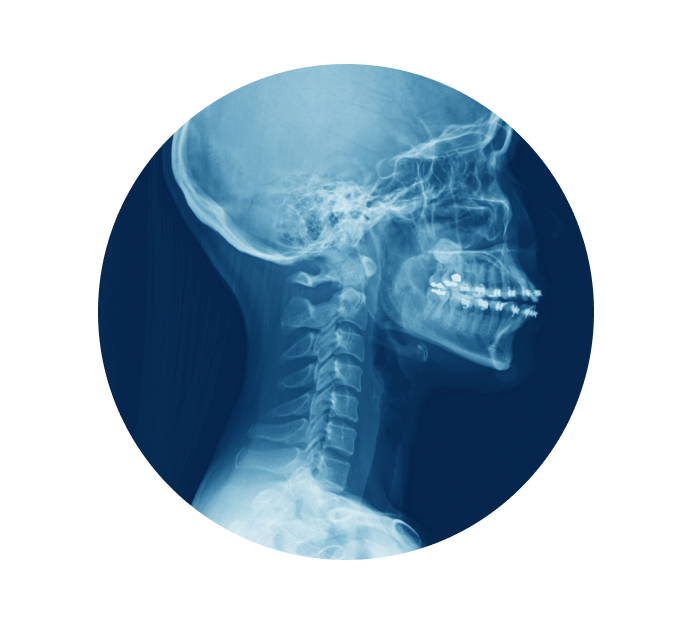

Рентген шейного отдела позвоночника в Краснодаре

Рентген шейного отдела позвоночника позволят выявить такие нарушения и заболевания как остеохондроз, показывает деформацию шейных позвонков, смещение дисков, растяжение, ушиб и не только. При патологиях костных структур этой области тела нарушается ее подвижность, появляются головные боли, нарушается работа вестибулярного аппарата.